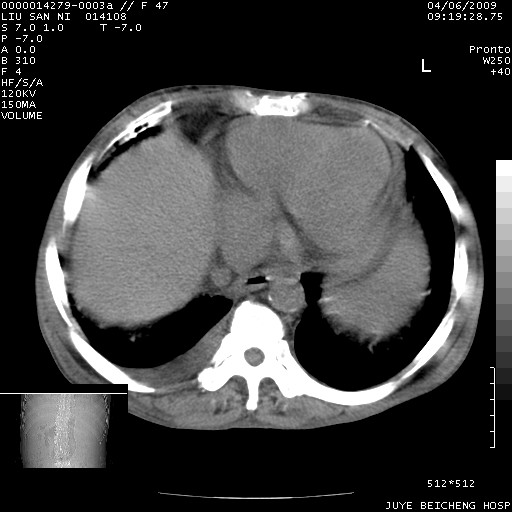

以下是引用前行在2009-4-7 10:31:00的发言:[br]肝脾肿大;双肾增大,双肾盂少量积水可能,肾膜膜增厚,肾周间隙增宽,并见桥间隔,提示结缔组系统疾病、系统性红瘢狼疮肾可能性大。继发右侧胸腔、心包、腹腔积液。